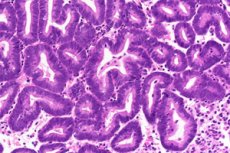

Гиперпластические процессы эндометрия (ГПЭ) - патологическая диффузная или очаговая пролиферация (утолщение) железистого и стромального компонента слизистой оболочки матки с преимущественным поражением железистых структур.

Выделяют три основных вида гиперпластических процессов эндометрия: эндометриальную гиперплазию, полипы эндометрия и атипическую гиперплазию (аденоматоз).

В 1994 г. ВОЗ была принята классификация гиперплазии эндометрия, основанная на рекомендациях ведущих гинекологов и патоморфологов, включающая гиперплазию без клеточной атипии и гиперплазию с клеточной атипией (атипическая гиперплазия эндометрия или аденоматоз). В каждой группе выделяют простую и сложную (комплексную) гиперплазию, в зависимости от выраженности пролиферативных процессов в эндометрии.

Полип эндометрия представляет собой доброкачественное опухолевидное образование, исходящее из базального слоя эндометрия. Патогномоничный анатомический признак полипа эндометрия - его основание «ножка». В зависимости от гистологического строения различают железистые (функционального или базального типа), железисто-фиброзные, фиброзные и аденоматозные полипы эндометрия. Для аденоматозных полипов характерна интенсивная пролиферация желез и их эпителия с относительно высокой митотической активностью. Аденоматозные полипы относят к предраковым состояниям. Железистые полипы наиболее типичны для репродуктивного периода, железисто-фиброзные - для пре- и перименопаузы, фиброзно-железистые и фиброзные - для постменопаузы.

С морфологических позиций к предраку эндометрия относят гиперплазию с атипией (атипическая гиперплазия) и аденоматозные полипы.

Гистологическое исследование соскобов слизистой оболочки матки - окончательный метод диагностики гиперпластических процессов эндометрия.